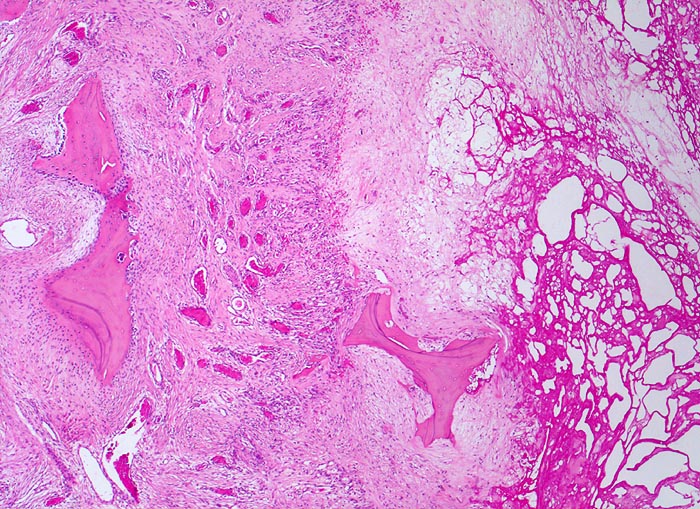

Der progrediente Knorpelverlust führt zum Freiliegen der knöchernen Deckplatte. Der subchondrale Knochen antwortet mit einer elfenbeinartigen Sklerose in Arealen vermehrter Belastung (=Eburnisation). Der traumatisierte subchondrale Knochen kann als Folge einer Knochennekrose pseudozystisch degenerieren (Geröllzystenbildung). Am Rand des Knochens, ausserhalb der Belastungszonen bilden sich irreguläre Knochenneubildungen (Randosteophytenbildung ev. mit Verdoppelung des Gelenkknorpels). Fragmentierungen dieser Osteophyten oder des Gelenkknorpels führen zu intraartikulären freien Körpern (=Gelenkmäuse) und einer Detritussynovialitis (> 1146) (> 1038) (> 539).

• Sekundäre Sklerose der freiliegenden Spongiosa mit Anbau von breiten Faser- und Lamellenknochensäumen an die alten Bälkchen.

• Randosteophyt, welcher über Resten des dort noch vorhandenen Gelenkknorpels entstanden ist (Verdoppelung des Knorpels).

• Nekrosebezirk in der Spongiosa (Geröllzyste) umgeben von einem Granulationsgewebssaum und Narbengewebe.